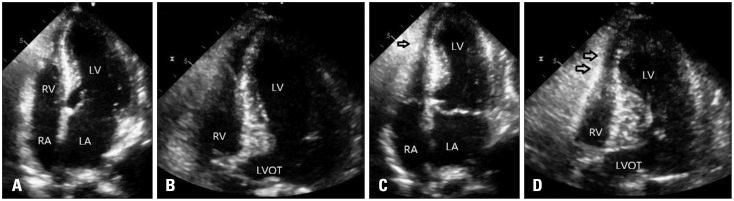

We describe a case of Takotsubo cardiomyopathy in an elderly woman after status epilepticus. In an emergency echocardiography, not only left ventricular apical ballooning but also right ventricular apical hypokinesia was observed. After a medical management, the patient's condition was improved and a follow-up echocardiography showed substantial recovery of left and right ventricular apical ballooning.

我们描述了一例老年女性在癫痫持续状态后发生的Takotsubo心肌病病例。在急诊超声心动图检查中,不仅观察到左心室心尖部气球样变,还发现右心室心尖部运动减弱。经过药物治疗后,患者病情好转,随访超声心动图显示左、右心室心尖部气球样变明显恢复。